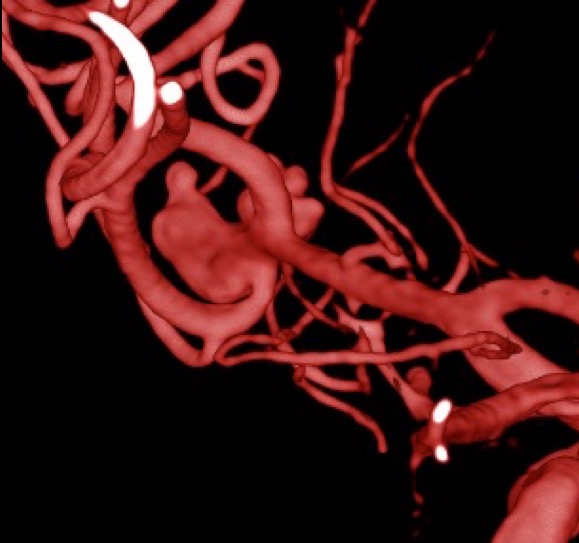

Fig. 2. TC de cerebro sin contraste post tratamiento: corte axial, evidenica artefacto metalico por material de embolización a nivel del valle Silviano izquierdo (circulo naranja).

Fig. 3. Angiografia digital 3D: Aneurisma sacular pequeño bilobulado, con pseudoaneurisma asociado, responsable del sangrado.